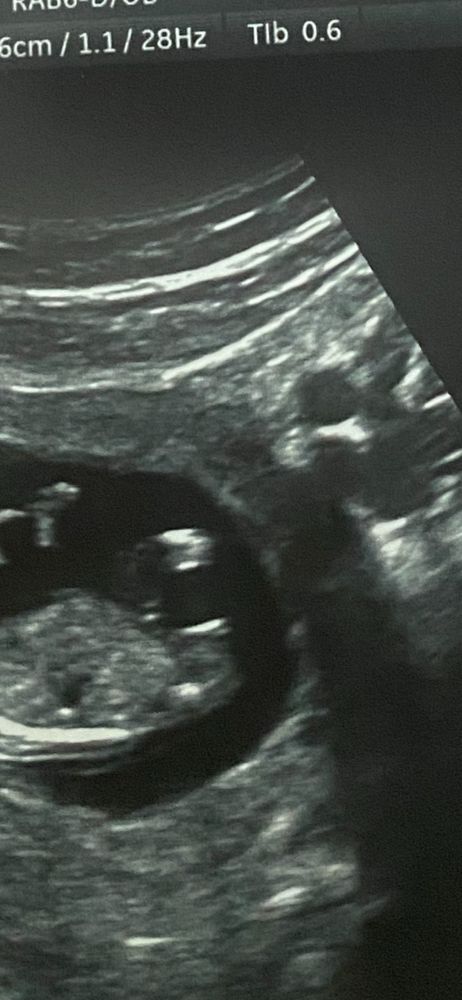

ПОЛ РЕБЁНКА!а вдруг тут есть те кто что то понимает и разглядит 😅

Пол малыша

Скрининг был на 12.3 дня сказала видеть пол на 80% гендар пати будет 1 июля а я все извелась 🙄скажите что я не одна такая кто на фотках рассматривает пол 🤣 типо как будто что то пойму

Кажется девочка. С дочкой так же бугорок выглядел. 1го числа отпишитесь, интересно))) ❤️

Тори Ак, буду ждать, я своего тоже разглядывала, но у вас прям видно что палочкой, это девочка, а пимпочкой в верх мальчик)))